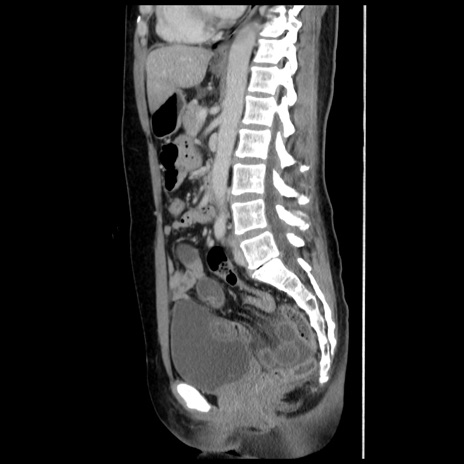

症例10(矢状断像)

【症例】 50歳代女性

【主訴】 腹痛

【現病歴】前日生レバーを食べた。今朝に排便あり。 昼前に突然発症の腹痛を生じ、当院救急外来を受診した。

【既往歴】 子宮筋腫にてで子宮全摘後

【身体所見】 意識清明、腹部:平坦、軟、下腹部やや左を中心に圧痛・反跳痛あり、筋性防御あり

【データ】WBC 7800、CRP 0.07